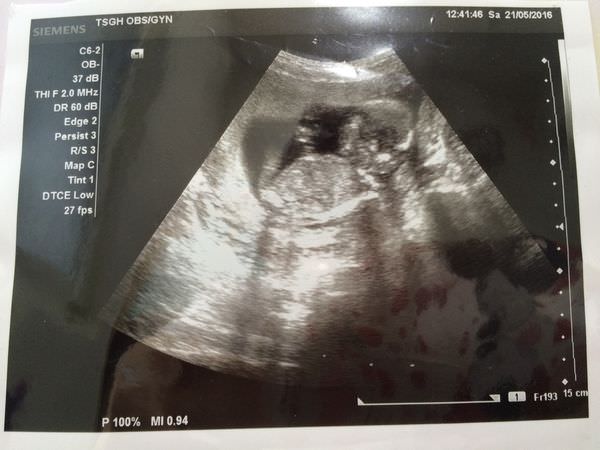

5/21(16W)

默默就已經來到四個月了,覺得時間過超快的啦!!!

這次產檢終於拿到第一張超音波照片瞜!!!

媽媽體重也增加了1KG

二寶也都在標準之內~~~很棒很棒